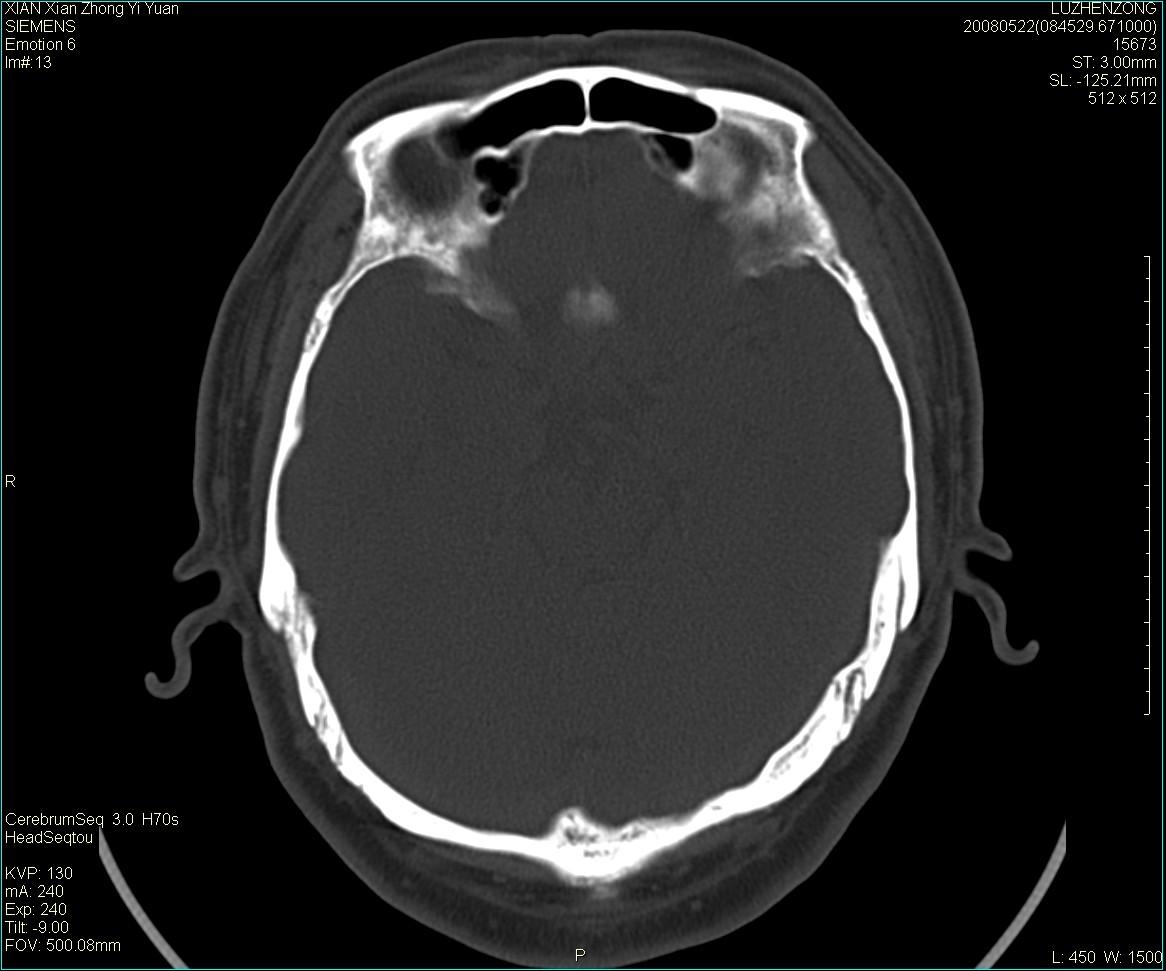

以下是引用gaoshengjiang在2008-5-28 19:06:00的发言:[br]考虑来源于蝶骨前床突区骨软骨瘤。

以下是引用卜一在2008-5-28 20:46:00的发言:[br]中颅窝“骨纤维异常增殖症”。不除外考虑来源于蝶骨前床突区“骨软骨瘤”。[br]

以下是引用liangshusheng在2008-5-28 20:13:00的发言:[br]单骨病变,考虑骨化性纤维瘤。